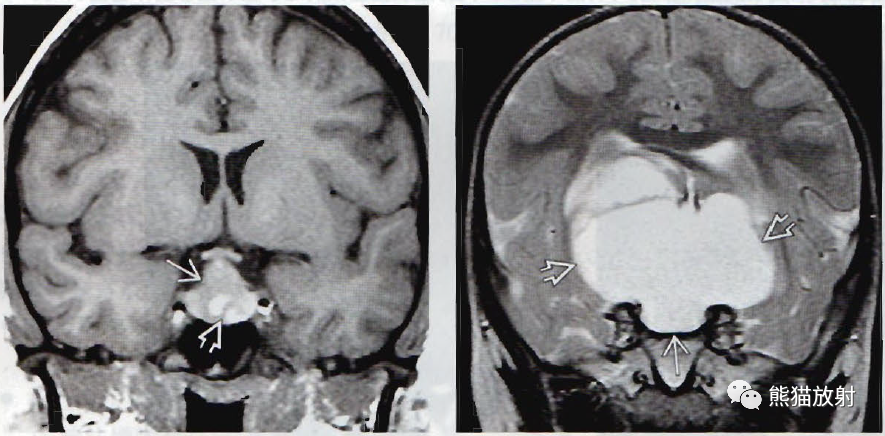

(左) 21岁女性,突发头痛、T4降低,冠状位T1WI MR显示高信号的肿块和更高信号的囊内结节。术前诊断为垂体卒中,术中发现为Rathke裂囊肿。

(右) 2岁儿童,冠状位T2WI显示位于鞍内和鞍上的巨大囊肿。手术发现为巨大的Rathke裂囊肿。